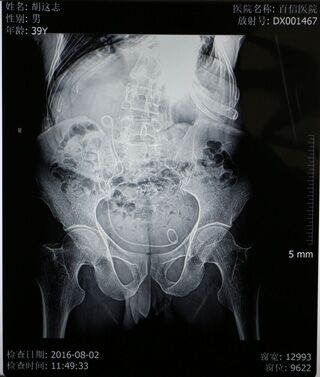

可这些也仅是体表上的显现,当丁主任拿到检查结果时是不免心头一紧——肌酐、尿素、尿酸等指标均超出正常指标数倍,已经开始呈现出尿毒症的检验结果及体征。患者的左肺已经从身体的右侧胸腔挤压到左侧胸腔,左侧肺功能已经有效消失,同时右侧肺功能也受到了影响,肺活量不到正常人的一半,呼吸很浅很快,并伴有呼吸性酸中毒,并且心脏功能很不好,平时还需要用药物来保持心率;但加严重的是患有结石的输尿管严重畸形,他的输尿管严重扭曲,左侧输尿管已蜿蜒扭转到身体右侧,从右侧延至膀胱。检查结果显示患者结石的位置还偏偏位于左侧输尿管上段,这也就意味着如果进行手术,则需要将输尿管镜一直蜿蜒延伸到输尿管的尽头才能进行,这些都使手术难度大幅度增加,在从医三十多年,临床经验非常丰富的丁主任看来,这个病例也是非常棘手的。

手术时间定于6月27日,经过严谨细致的术前准备,由丁德刚主任为患者进行钬激光碎石清石术的治疗。考虑到患者身体情况特殊的情况,麻醉师采用呼吸管来人工控制患者呼吸,并用药物控制心率,并且医生还人工造截石位来帮助患者保持术中平衡。丁主任凭借多年的手术经验,采用输尿管镜配合钬激光,一一清除患者输尿管内的结石,在经过两个小时的辛苦努力后,手术终于圆满的完成了。当胡先生醒来听到“手术很”的消息后,喜极而泣,不停地说:“我都没敢想能再好起来,多亏了你们,多亏了你们啊!”

8月2日是胡先生到医院进行术后拔管的日子,鉴于胡先生的家庭生活状况,院方决定免除拔管手术的所有费用,为胡先生免费进行后续手术,并为胡先生买好了回程的火车票,让胡先生能够加安心的回家。胡先生此时没有说一句话,但是那颤抖的双手和眼中的泪光足以表达出他内心的感激之情……